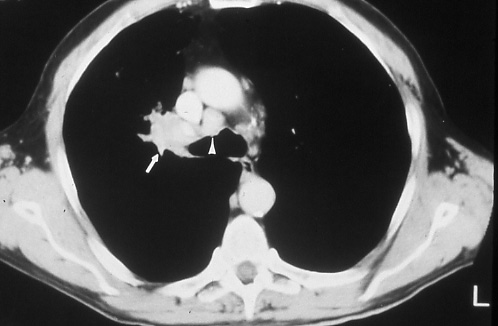

Fig. 44b: Computed tomographic scan of the chest shows the right hilar mass (arrow) and right paratracheal adenopathy (arrowhead). There is a suggestion of compression of the right main stem bronchus anteriorly, T2 N2 M0, stage IIIA disease.